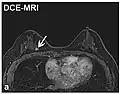

| Dynamic contrast enhanced | DCE | Measures changes over time in the shortening of the spin–lattice relaxation (T1) induced by a gadolinium contrast bolus.[27] | Faster Gd contrast uptake along with other features is suggestive of malignancy (pictured).[28] |

| |

- Dynamic contrast enhanced (DCE): Measuring shortening of the spin–lattice relaxation (T1) induced by a gadolinium contrast bolus.[46]